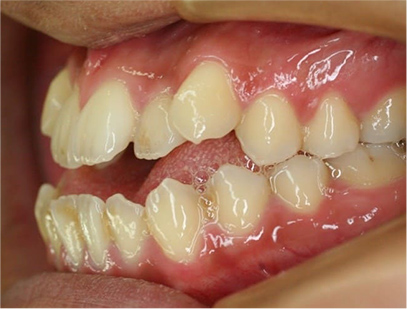

前歯が咬み合っていなく反対咬合の症例

上下の前歯が咬んでない事を主訴として来院されました。通常どおり検査を行い「前歯部に開咬を伴う反対咬合」と診断されました。

治療計画

上顎は左右4番目の第一小臼歯を抜歯して、また下顎も左右4番目の第一小臼歯を抜歯してその抜歯されたスペースを利用して前歯を上下それぞれ綺麗に並べて咬み合わせを改善する事にしました。また前歯を咬み合わせるためにゴムを使用する事にしました。

治療前

• 右側

• 左側

治療前の写真と治療後の写真を比べると口元が治療前は下唇が出ていて、鼻の下が凹んでいました。上顎の前歯のデコボコも綺麗に並びました。また、上下の前歯は開咬が治りしっかりと咬み合ってます。

治療期間は患者様の協力が大変に良かったために2年半とさほど長くはありませんでした。